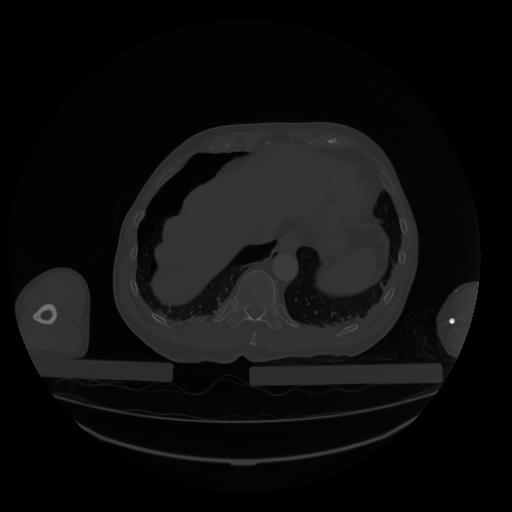

28 CUERPO,CE,Vol,2.0,CUERPO,,